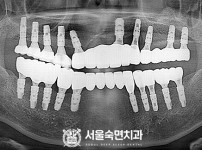

임플란트-전후사진4

임플란트-전후사진5